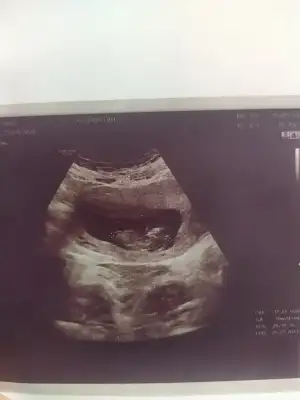

Kizlarr anlayan varsa yorumlayabilir misiniz rica etsem 😊

Oy maşallah 🥰🧿 ama valla anlamadım 😅 2 hafta sonra görüşelim lütfen bebecik 😁🥰

Ay bencede 😂 2 hafta önce gittğimde hiç göstermemişti bu sefer de net bir görüntü yok yine bekleyelim bakalım 🤭 Bide bunu instagramdaki cinsiyet tahmini yapan sayfaya attım kesin oda bilemicek 😂😂😂